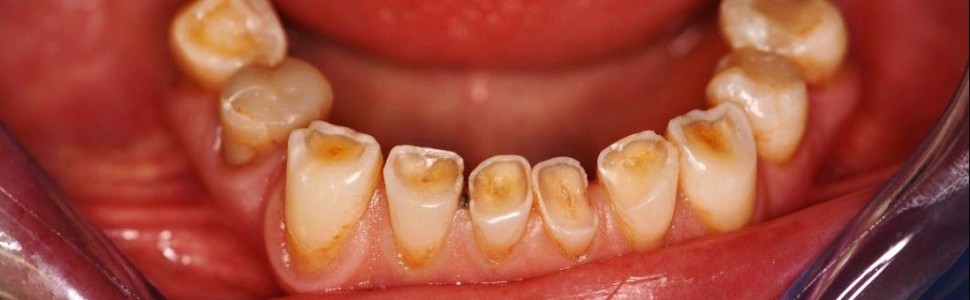

Starcie patologiczne to postępująca utrata tkanek twardych zębów przekraczająca normę przyjętą dla danego wieku, spowodowana czynnikami niepróchnicowego pochodzenia. Rehabilitacja pacjentów z patologicznym starciem zębów wymaga wiedzy i umiejętności lekarza praktyka. Ułożenie indywidualnego, często wielospecjalistycznego, dobrze przemyślanego planu leczenia ma znaczny wpływ na jego skuteczność. Istotna jest dokładna analiza etiologii schorzenia, ocena okluzji pacjenta i kwalifikacja do leczenia endodontycznego zębów ze znacznym starciem. Ważne jest również odpowiednie postępowanie protetyczne – po przeanalizowaniu wad i zalet każdego z rozwiązań.